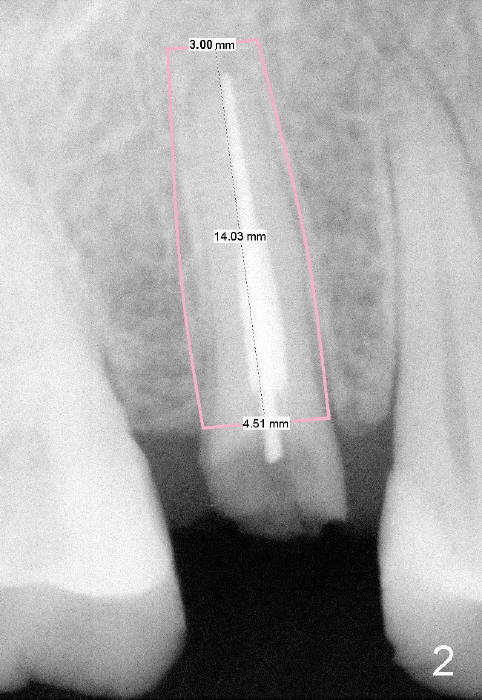

A 51-year-old man has several missing teeth in the maxilla restored by a partial denture. The tooth #4 fractures (Fig.1) and is planned to be restored by an implant (Fig.2 design: 4.5x14 mm). Immediately post extraction, osteotomy is initiated by a 2.0 mm pilot drill at the depth of 14 mm (3 mm into new bone, Fig.3). Finally a 4.5x14 mm SM (submerged) implant is placed with insertion of a 5.2x5(3) mm healing abutment (Fig.4). Mixture of autogenous bone and demineralized cortical allograft is placed in the gap between the buccal plate and the implant/abutment (Fig.6), covered by collagen membrane (Fig.7 M; P: partial denture). In fact the membrane is fixed between the implant and the healing abutment lingually. The wound is finally covered by perio dressing (Fig.5 ^). The patient returns 5 days postop. The perio dressing is removed unintentionally. It appears that the membrane has started to be resorbed (Fig.8).